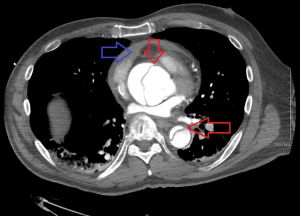

Dissection of the aortic arch: initial CXR normal visualization of the calcification shadow in the aortic arch (left); CXR 4 months later with calcification shifted centrally into the shadow of the aortic arch with a blurred external border (middle); CT scan coronal (top right) and axial (lower right).